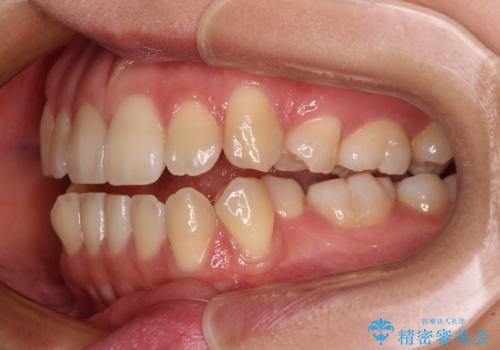

- 上下顎前歯部の非接触(開咬)と下顎のデコボコを主訴に来院された患者様です。

右側上下と左上の小臼歯が一本ずつ少なく、さらに骨格的な左右差もあり上下の真ん中の位置がずれています。

下顎のデコボコの解消と、真ん中の位置を改善するために左下の小臼歯を抜歯することとしました。

舌のトレーニングは継続して行ってもらっているため、開咬や抜歯したスペースの後戻りはなく、経過は良好です。